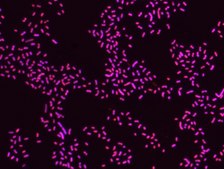

Proteus probe specifically recognizes Proteus species (see images of Proteus vulgaris and Proteus mirabilis). Moreover, it was shown that this probe recognizes Proteus penneri and Proteus hauseri.16

FISH technique was successfully used for clinical detection of Proteus spp. in artificial urine medium and urine samples from patients with UTIs. The probe was able to detect 11 strains of P.mirabilis, 6 strains of P. vulgaris, 2 strains of P.penneri and one strain of P. hauseri.16 The probe can also be used to detect P. mirabilis and P. vulgaris pure culture (as described in the figure legends). FISH can also be implicated to detect Proteus spp. in colon sections embedded in paraffin.17,18 Moreover, FISH can be implicated to identify Proteus spp. in the gut of the medicinal leech.19

Probe for fluorescence in situ hybridization (FISH),recognizes Proteus vulgaris and Proteus mirabilis cells.